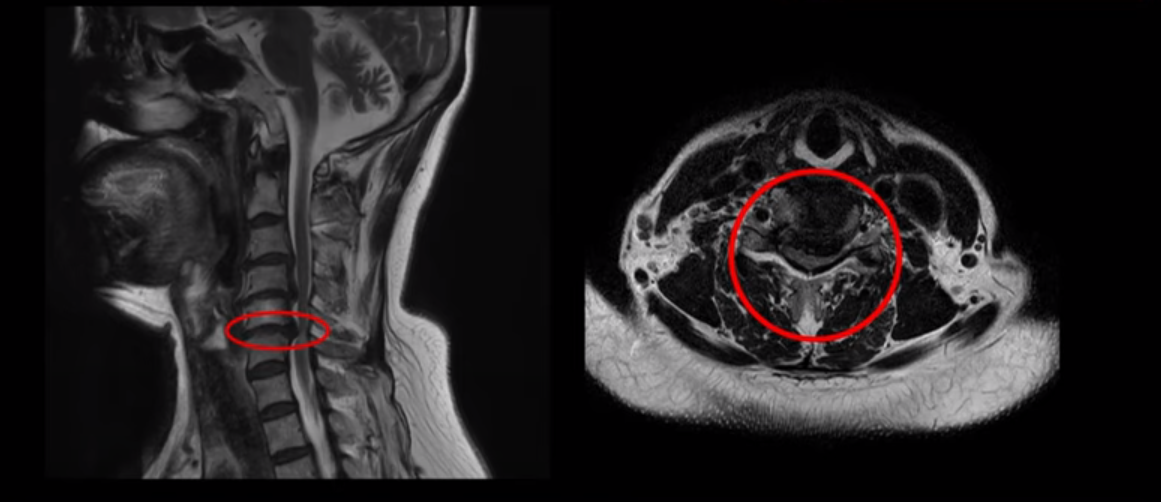

이 환자분은 목디스크 5번, 6번에 심한 디스크로 인해 경추척수증이 발생한 환자입니다. MRI에 보시는 것처럼 디스크가 심하게 밀려나와 이로 인해 척수신경이 눌려 신경손상이 하얗게 보입니다.